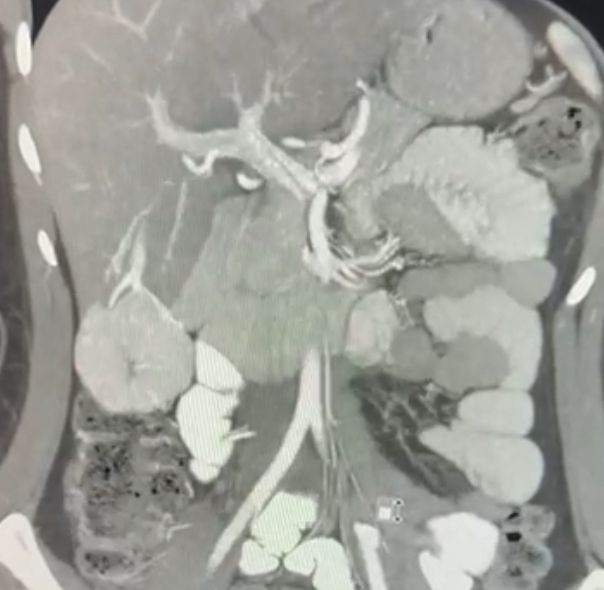

A 30 year old lady presented to us with recurrent abdominal pain due to a liver tumor. Patient was thoroughly investigated with CT & MRI scans. Tumor markers like AFP, Ca19-9 & CEA were done. All tests pointed to a benign liver tumor. Since there was no ambiguity in imaging diagnosis, a biopsy was avoided and decision to proceed with surgery was taken. The patient was fit for surgery and tumor location was ideal for a laparoscopic surgery wherein the tumor was removed along with a small margin of liver. Patient was discharged by 6th postoperative day.

Laparoscopic liver surgery is ideal in small, peripherally located tumors. However can be done even for large deep seated tumors depending upon surgeon experience.